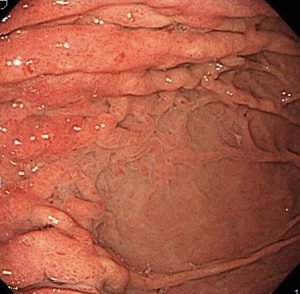

レントゲンで言われたように、胃の上部のひだが肥厚して腫れあがっています。

胃の壁は硬くなっていて、スコープで空気を入れてもこれ以上は広がりません。

これは「スキルス胃がん」です。

胃の粘膜下を這うようにしてがんが全体に進行するために、胃の壁が硬くなり広がらなくなります。

胃の上部から真ん中・出口近くまで、がんが粘膜下を這っています。